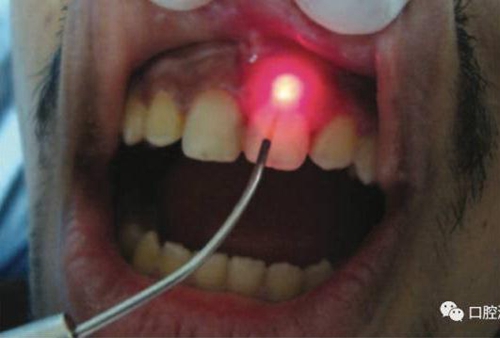

對(duì)瘺管位置進(jìn)行激光氣化

氣化消融發(fā)炎組織:利用高強(qiáng)度激光對(duì)根尖區(qū)域的腫脹、肉芽組織加熱使之氣化。如果發(fā)現(xiàn)有瘺管存在,可以將激光光纖插入瘺管中,采用間歇式發(fā)射激光的方式,邊發(fā)射激光,邊抽出光纖。此時(shí)務(wù)必注意激光功率不宜過高,而且光纖抽出速度不宜太慢或太快,以出現(xiàn)水汽為宜。